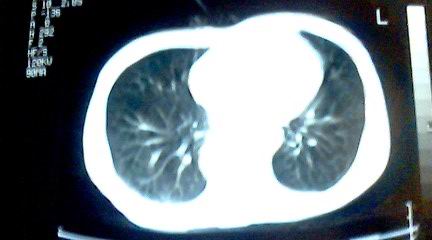

标题: CT25218:请教!胸部CT,胸8椎体骨质破坏,伴周围软组织肿。

患者,女41岁,肢体乏力。

双肺及胸椎结核。

两肺上叶继发性肺结核;胸椎结核并椎旁寒性脓肿形成。